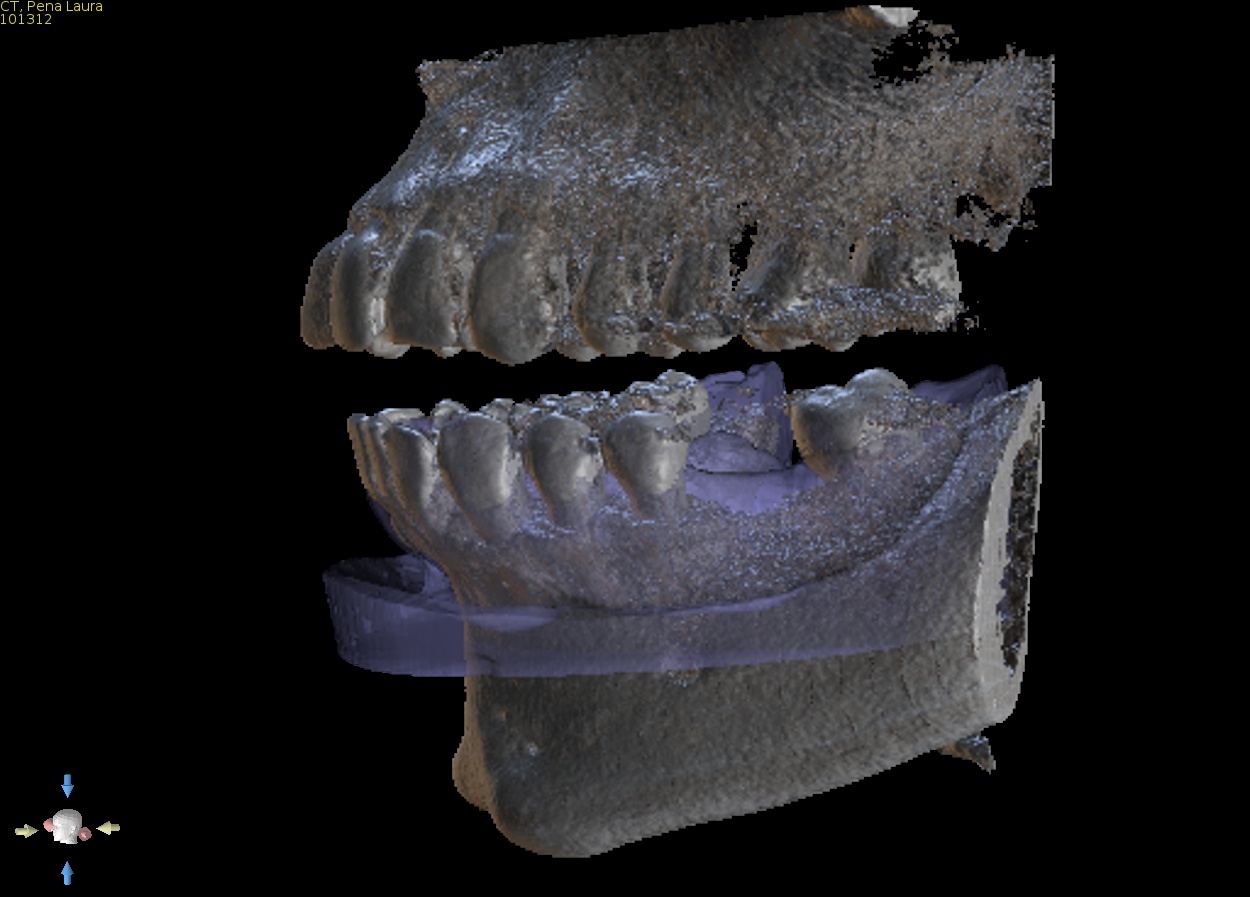

3. Approval of implant report

Approve the plan so construction of the implant guide can go ahead, this must be done via replying to our email. Let us know what type of guide you wish to select and what size of drills you will be using. See next point for more information on types of guides.

Approve final implant report via email.